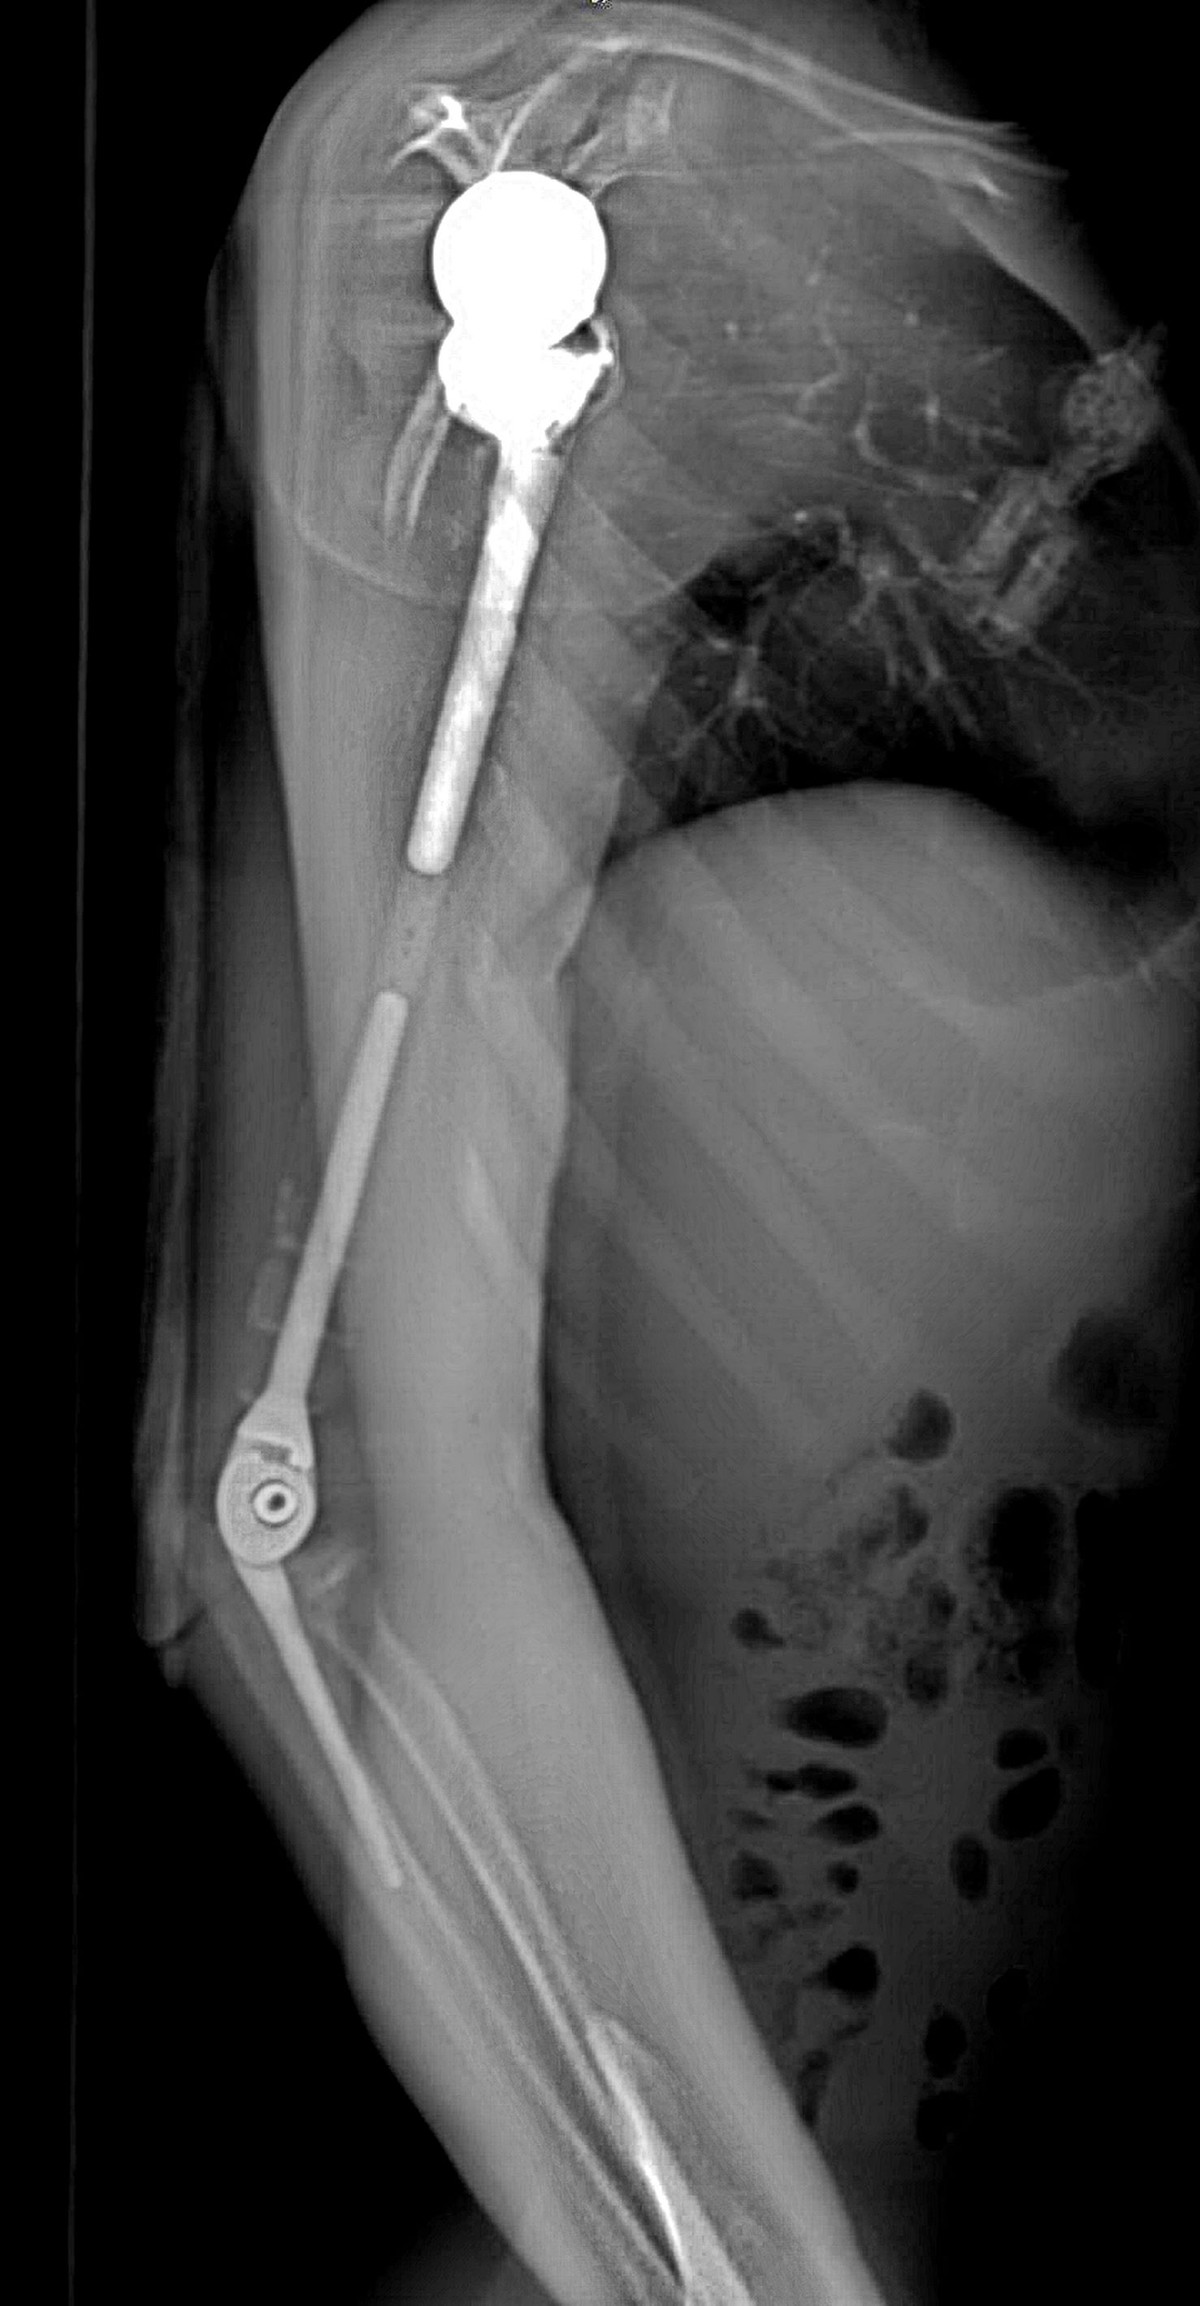

Ảnh chụp X-quang tay phải của bệnh nhân sau khi phẫu thuật thay xương toàn bộ cánh tay

Nhóm phẫu thuật đã lên kế hoạch sử dụng các công nghệ trong tái tạo xương hiện đại nhất hiện nay bao gồm tái tạo lại cấu trúc khớp vai, cấu trúc khớp khuỷu bằng vật liệu hợp kim titan. Đặc biệt, đội ngũ bác sĩ của Trung tâm đã có một quyết định định táo bạo: không sử dụng hoàn toàn vật liệu kim loại mà chế tạo phần thân xương cánh tay sử dụng công nghệ in 3D vật liệu polyme sinh học (PEEK).

Vật liệu này do phòng nghiên cứu ứng dụng công nghệ in 3D của Đại học VinUni sản xuất, giúp kết nối phần khớp vai và khớp khuỷu với nhau, đồng thời phục hồi lại điểm bám của các gân cơ quanh cánh tay. Đây được coi là một quyết định đầy tính sáng tạo dựa trên những nghiên cứu và thử nghiệm chuyên sâu từ nhiều ca bệnh đã thành công của ê-kíp phẫu thuật.

Đặc biệt, công nghệ in 3D được coi là công nghệ duy nhất hiện nay mang lại khả năng cá thể hóa các chi tiết cấy ghép. Nhờ công nghệ này, cả 3 phần của xương cánh tay nhân tạo đều được “thiết kế riêng” theo đúng kích thước cánh tay thật của bệnh nhân, đồng thời có các điểm cố định giúp khôi phục lại hệ thống gân cơ bám xương.

Trước khi sản xuất, tất cả những thiết kế này đều được thử nghiệm mô phỏng khả năng vận động, chịu lực trên máy tính. Nhờ vậy, xương nhân tạo sau ghép sẽ tương thích tối đa, “hoàn toàn vừa vặn” với cơ thể người bệnh và thời gian phục hồi chức năng vận động của cánh tay sẽ được rút ngắn đáng kể.